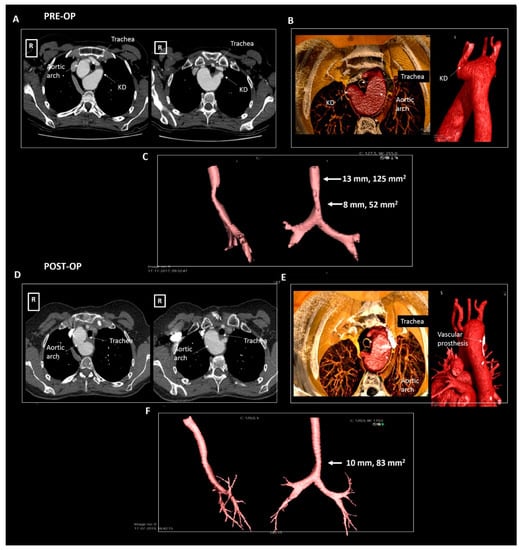

| Patient 3 | 50 | Female | Right-sided arch, aberrant LSA and KD | Symptomatic tracheal and esophageal compression | 30 × 29 mm, 870 mm2 | Dysphagia and dyspnea | Surgical resection |